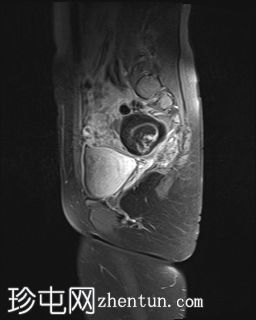

MRI扫描

矢状扫描

T2

右侧附件区可见较大囊性肿块,内含脂肪和液体,大小约为86毫米 x 60毫米。右侧血管蒂扭转,呈漩涡征。右侧卵巢可见增大充血的卵泡,为囊性肿块病变。左侧卵巢正常。